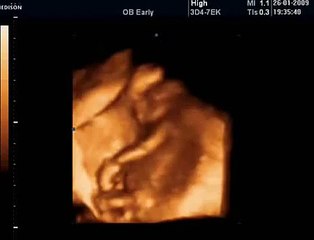

Amerika Birleşik Devletleri'nde yaşayan bir kadın, ikiz bebeklerine hamile olduğu sırada yeniden hamile kalmanın şaşkınlığı yaşadı. Doktora gittiği sırada ilginç gerçeği öğrenen kadın, başına gelenleri sosyal medya hesabından anlattı. brpABD'de yaşayan bir kadın, tıp dünyasında eşine az rastlanan bir olay yaşadı. TikTok hesabından paylaşımda bulunan @tamingtriplets adlı kadın, ikiz bebeklerine hamile olduğu sırada öğrendiği ilginç gerçeği takipçileriyle paylaştı. pDOKTOR ULTRASONA BAKINCA ŞAŞIRDIpGenç anne, rutin kontrolleri için doktora gitti. Ancak doktor, ultrason görüntüsüne baktığında bir terslik olduğunu hemen fark etti. Çünkü ikiz bebeklere hamile olduğu bilinen kadının karnında 3 bebek birden vardı. Çünkü genç kadın, hamileyken hamile kalmıştı. pBÜYÜK SEVİNÇ YAŞADILARpDoktorun haberi kendilerine bir anda verdiğini belirten tamingtriplets, "Doktor bizi bu duruma hiç hazırlamadı ve direk 3. bir çocuğumuz daha olacağını söyledi.